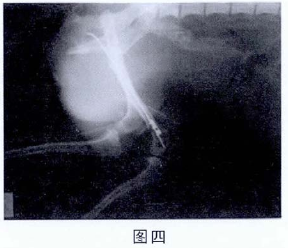

4.3.4术后拍X光片(见图四)。